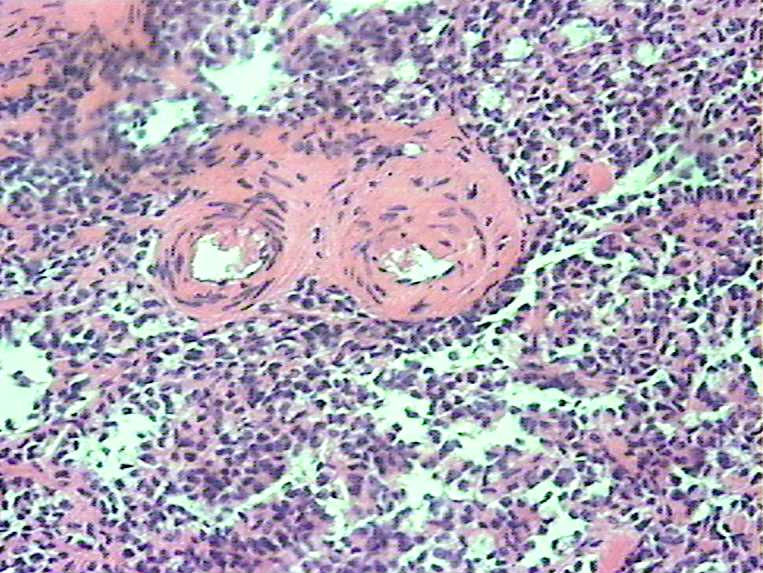

胰腺肿物 大体:灰白色肿物一枚大小:3*2*2cm,切面实性,质中。女,52

• 胰腺肿瘤图2

图2

胰腺实性-假乳头状瘤

实性假乳头状瘤

胰腺实性-假乳头状肿瘤(低级别恶性肿瘤)

会诊实性假乳头状瘤

胰腺实性-假乳头状肿瘤

胰腺实性假乳头状瘤